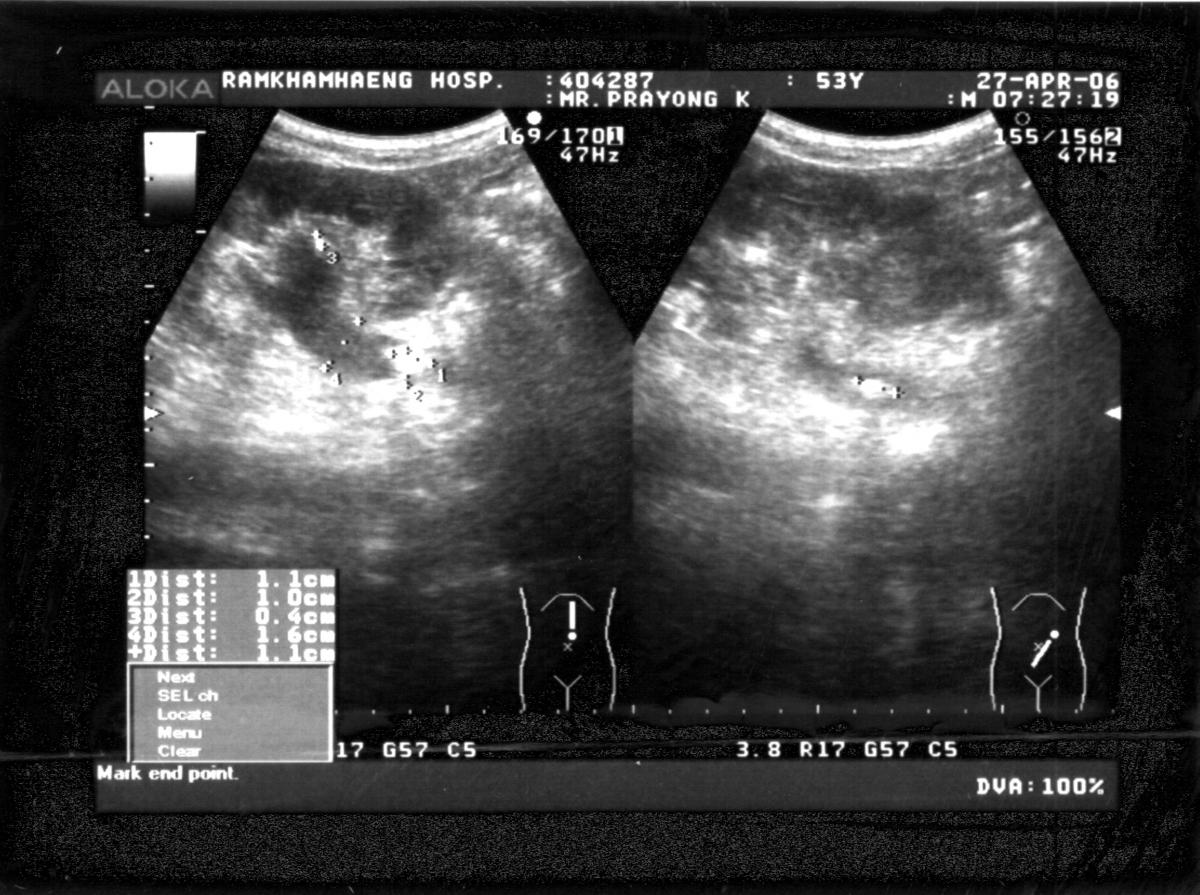

ภาพที่ 1. ภาพถ่ายรังสีของผู้ป่วยรายที่ 1.

ชายไทยคู่ อายุ 53 ปี มีประวัติปวดหลังและเอวด้านซ้ายมานาน 1 ชั่วโมง ปวดอย่างรุนแรงบริเวณเอวด้านซ้าย. การตรวจภาพถ่ายทางรังสีดังภาพที่ 1.

1. Ultrasonogram ของท้องด้านซ้ายบน.

2. กรวยไตและท่อไตส่วนบนด้านซ้ายโป่งและมีเงาจาก high echo ขนาด 1.1 ซม. ลอยอยู่ในท่อไตซ้ายส่วนบน อุดทางเดินปัสสาวะส่วนบนซ้ายทำให้เกิดอาการปวด.

3. นิ่วท่อไตซ้ายส่วนบน.